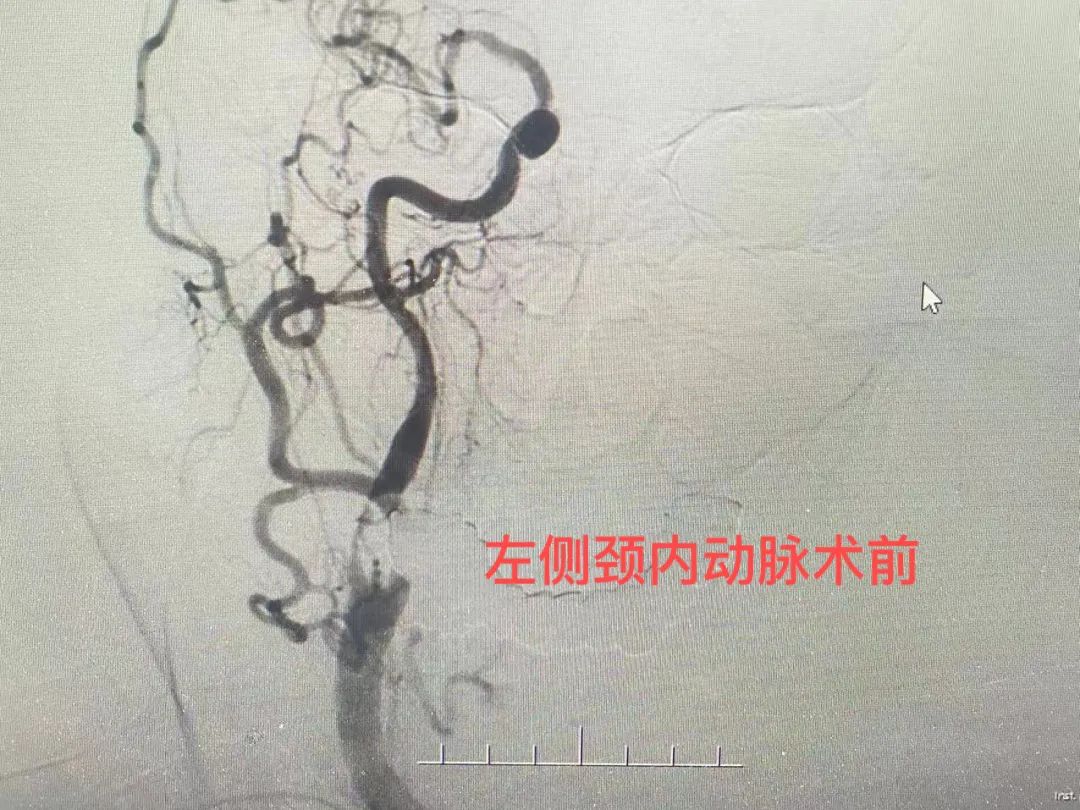

患者赵先生,今年90岁,因阵发性头晕3小时入院,既往高血压、冠心病、肺气肿病史,入院后完善颅脑磁共振提示双侧颈内动脉重度狭窄。

在完善相应检查后,神经内科团队全面评估患者情况,制定了完善的手术计划,在征得患者同意后,行脑血管造影术,术中行右侧颈内动脉球囊扩张术+支架植入术,术后患者安然返回病房。